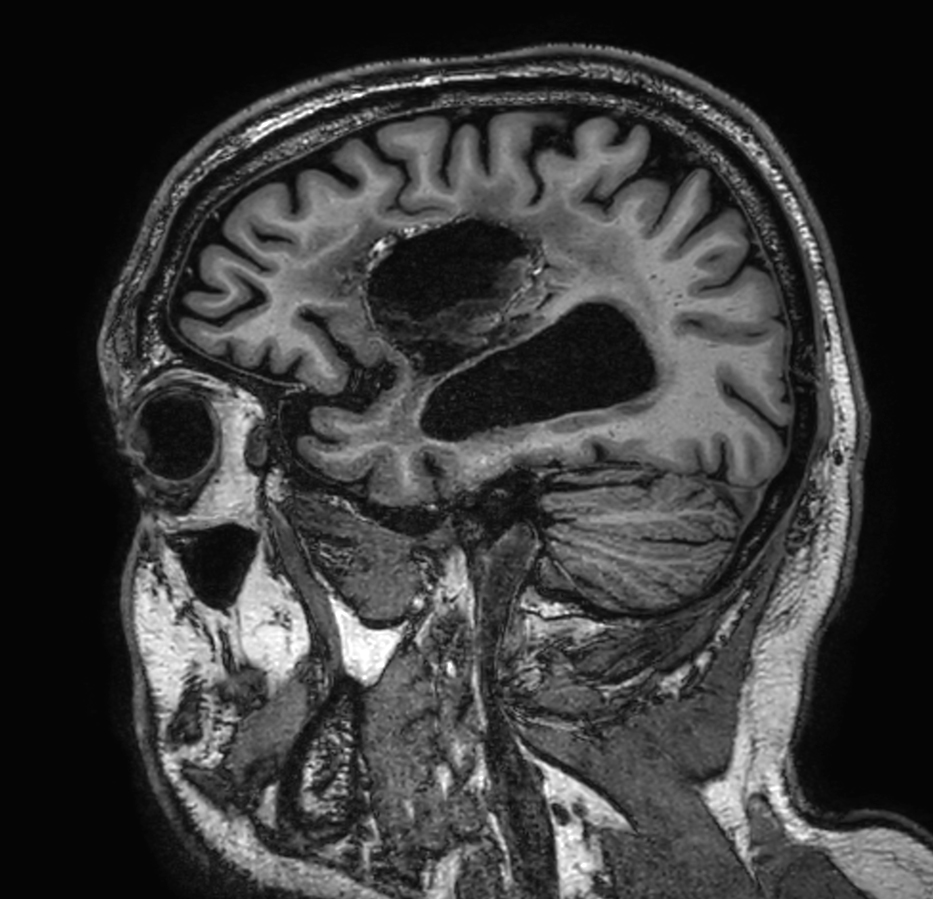

Brain glioblastoma, post-operative

Patient who was operated on glioblastoma

Sagittal 3D FLAIR